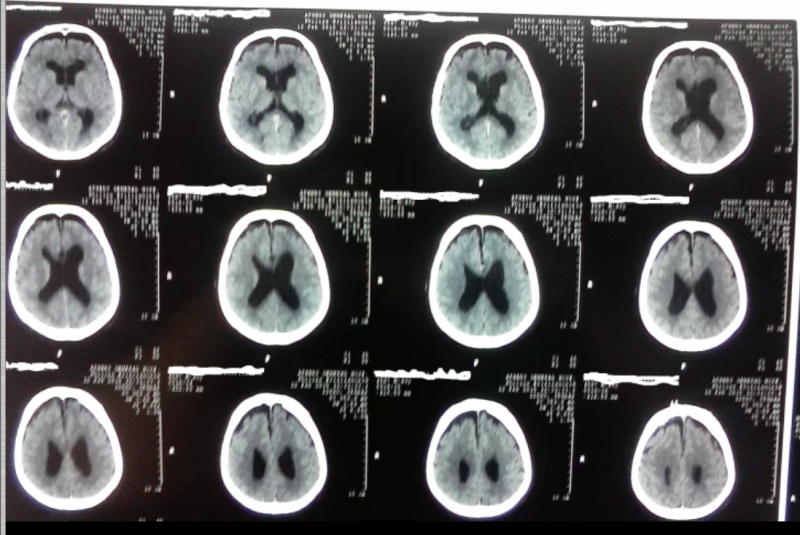

Ο ασθενής εξήλθε από την κλινική μας την τρίτη μετεγχειρητική ημέρα με σαφή βελτίωση των διαταραχών πρόσφατης μνήμης, συγκέντρωσης και βάδισης. Ο μετεγχειρητικός έλεγχος με αξονική τομογραφία εγκεφάλου ανέδειξε πλήρη αφαίρεση της εξεργασίας.

Μετεγχειρητικός απεικονιστικός έλεγχος